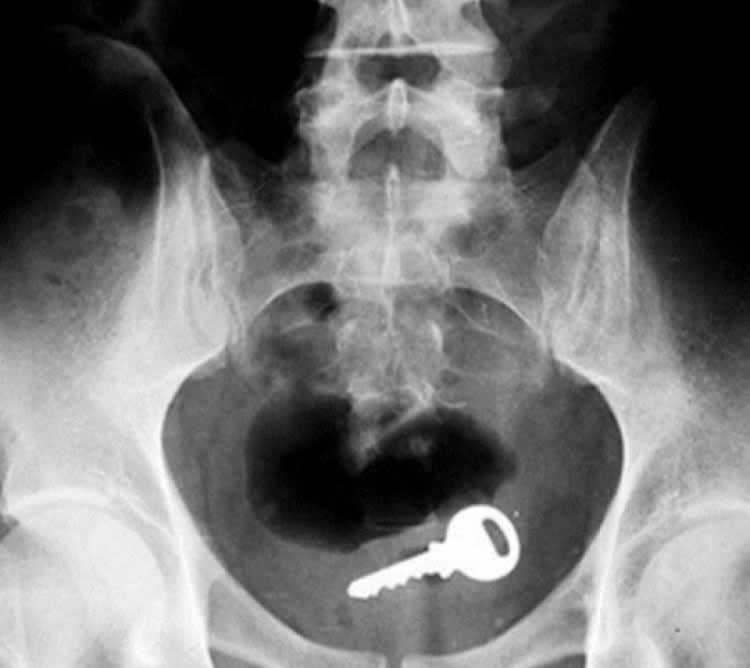

regardez moi ça 

Quelqu'un a t il perdu ses clés ?